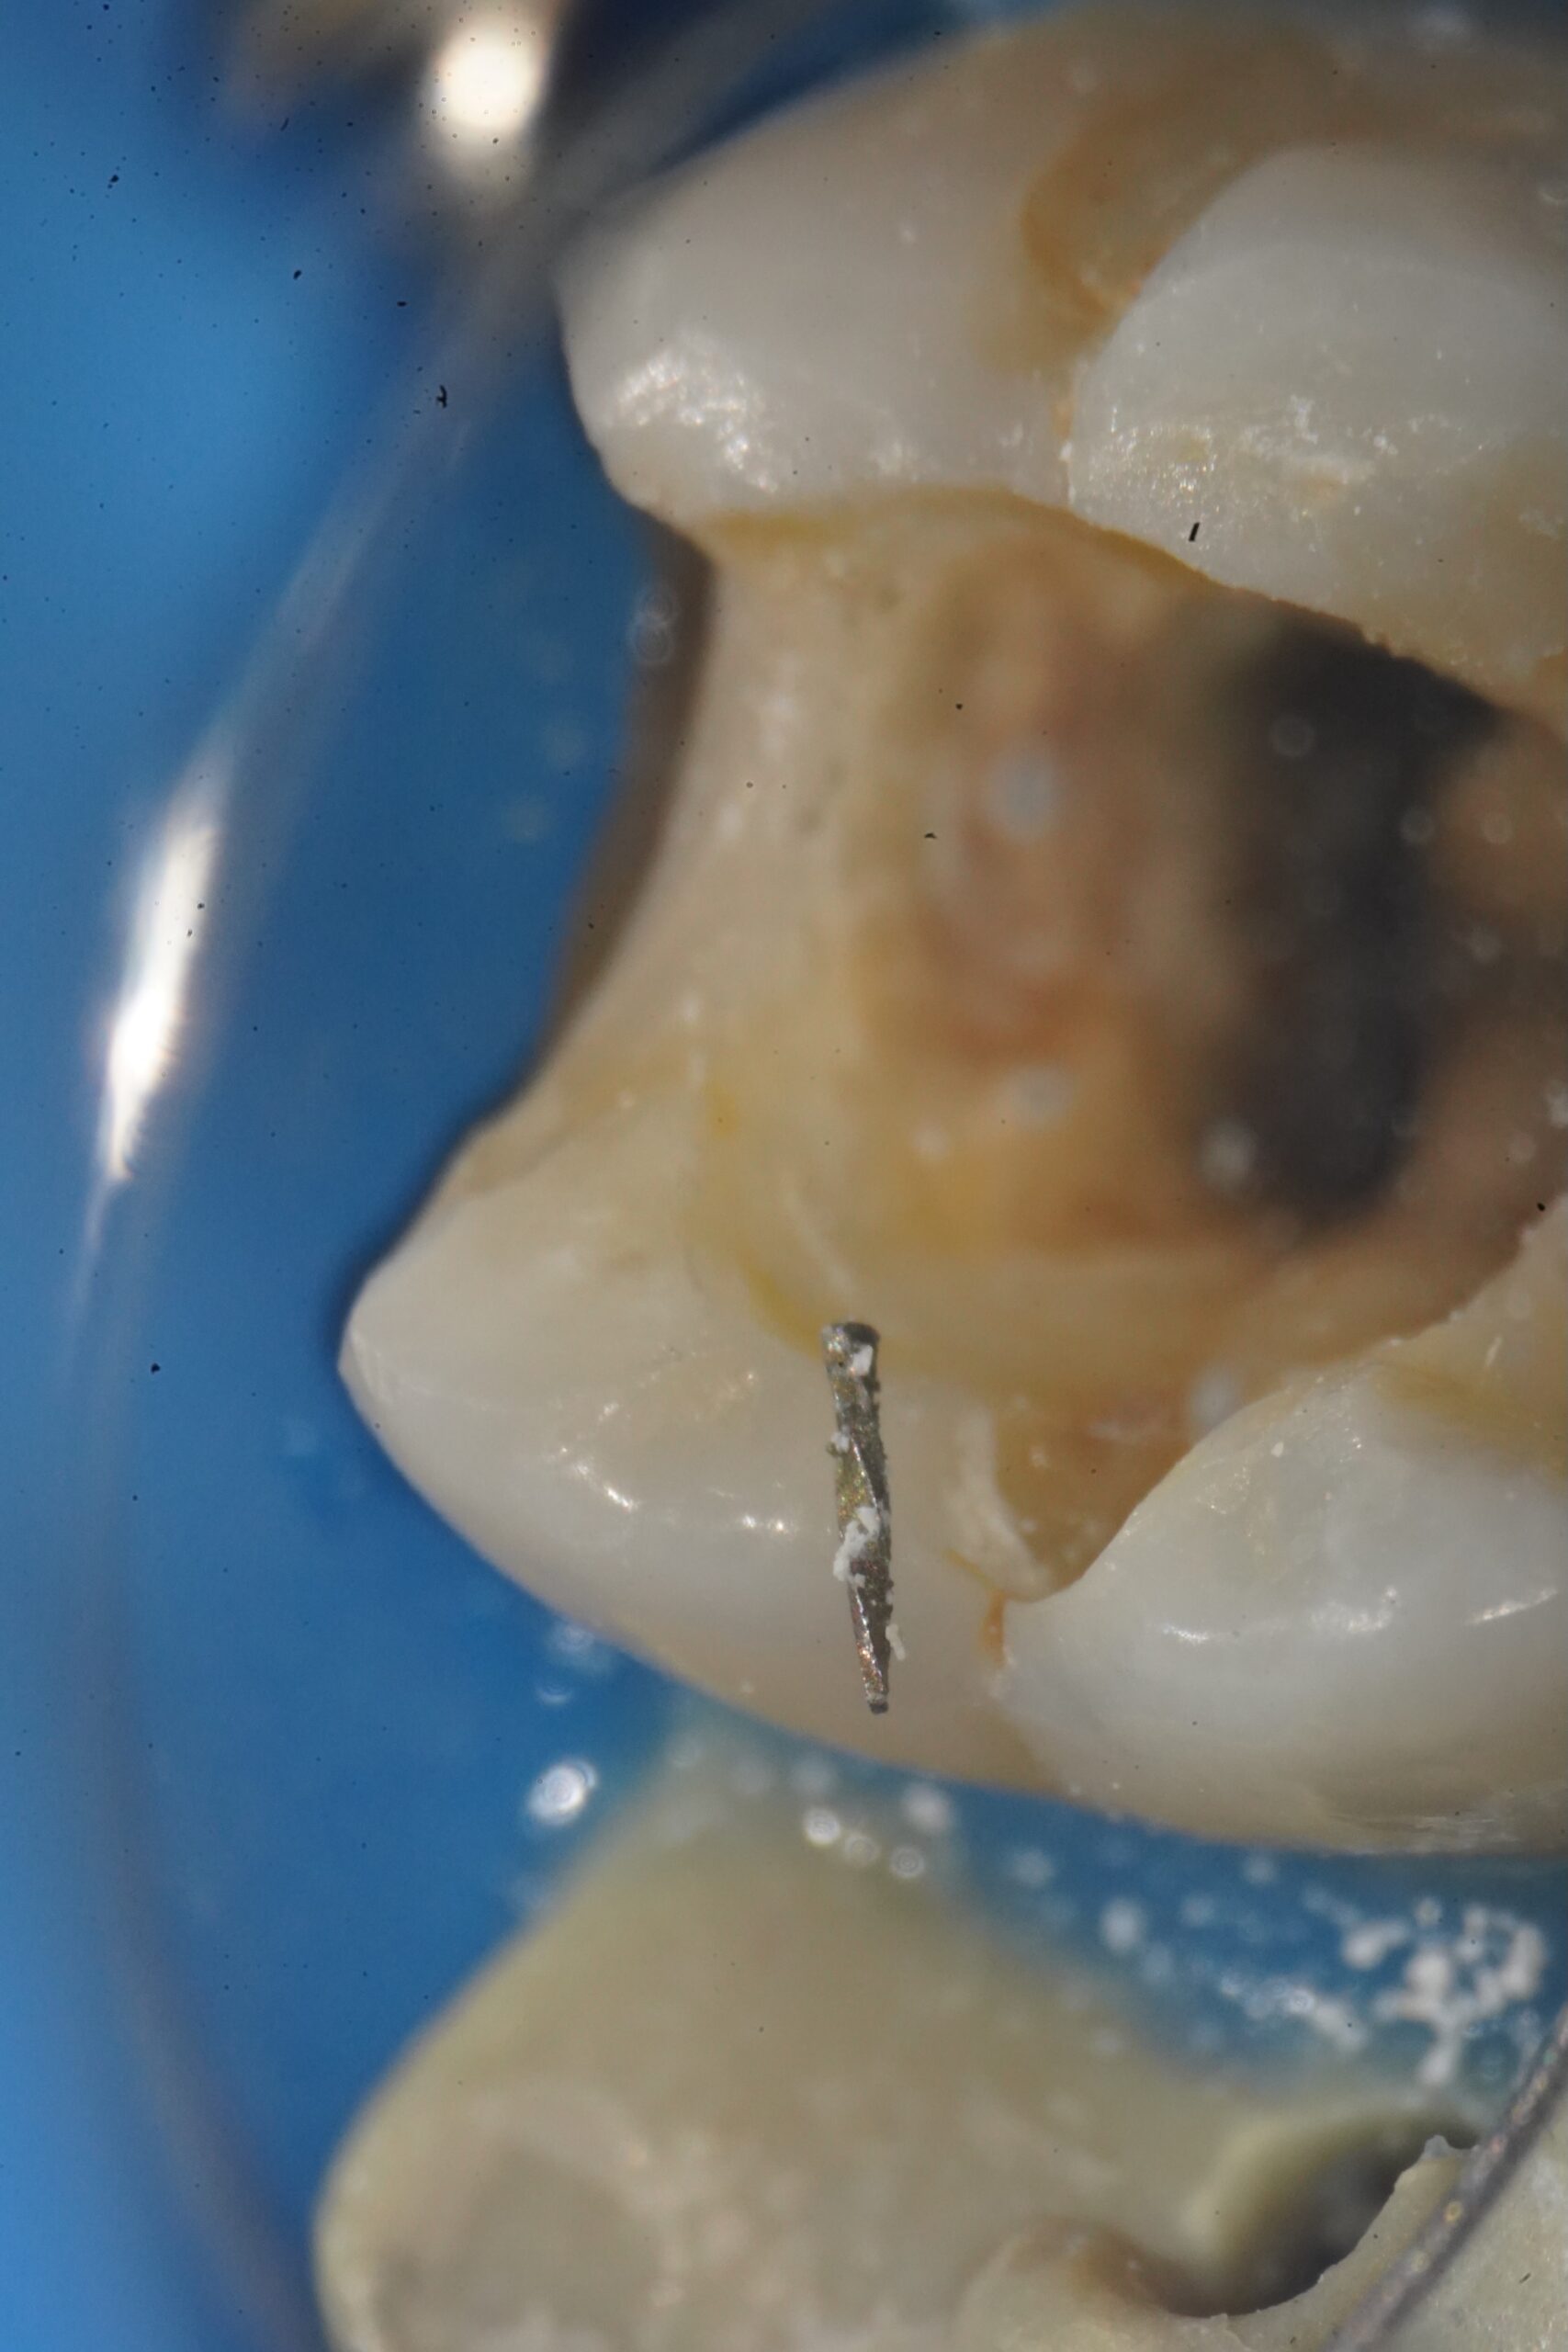

治療後

「他院で根管治療をしたが、中にファイルが残っていると言われた」——当院にもよく寄せられるご相談です。器具破折は拡大視野で丁寧に行っても稀に起こる根管治療の偶発症。重要なのは、感染の有無と位置を正確に評価し、歯を守れる選択を行うことです。

バイパス形成(Bypass)

極細ファイルで折片の脇に通路を作り、根尖まで洗浄・封鎖を可能にします。歯質の削除量が少なく、予後良好を狙える方法。

超音波+マイクロでの除去

顕微鏡下で視認し、超音波チップで振動・緩みを作って摘出。頸部〜中間サードで直線化できるケースに有効。